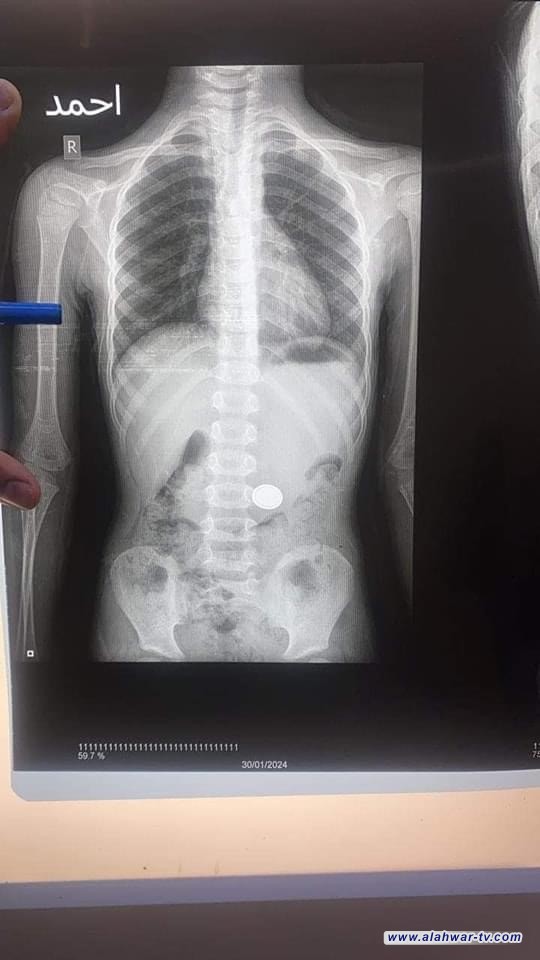

تمكن فريق طبي في مركز امراض الجهاز الهضمي والكبد في مستشفى الامام الحسين التعليمي من انقاذ حياة طفل بعمر ٦ سنوات، وقال رئيس الفريق اخصائي امراض الجهاز الهضمي الدكتور فائز خلف ال سرحان ان المريض ادخل للطوارئ بعد ابتلاعه لبطارية وتم اجراء الفحوصات من الرقائق الشعاعية وتحديد مكان استقرار البطارية،

مضيفاً ان المريض اجري له ناظور Mesh intervention endoscopy حيث يتم استخراج البطارية من بطن المريض في صالة عمليات الناظور التشخيصي والعلاجي